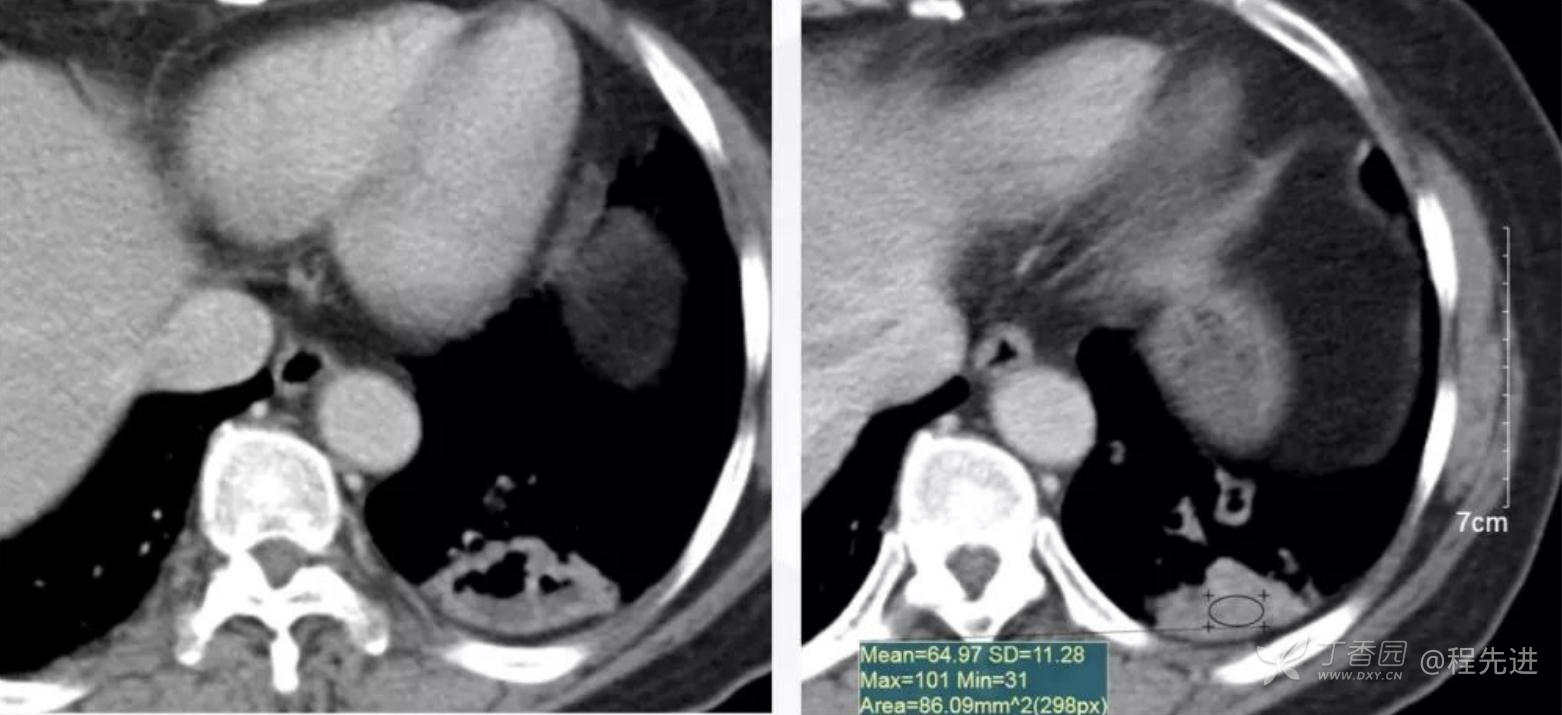

纵隔窗平扫

增强动脉期

静脉期